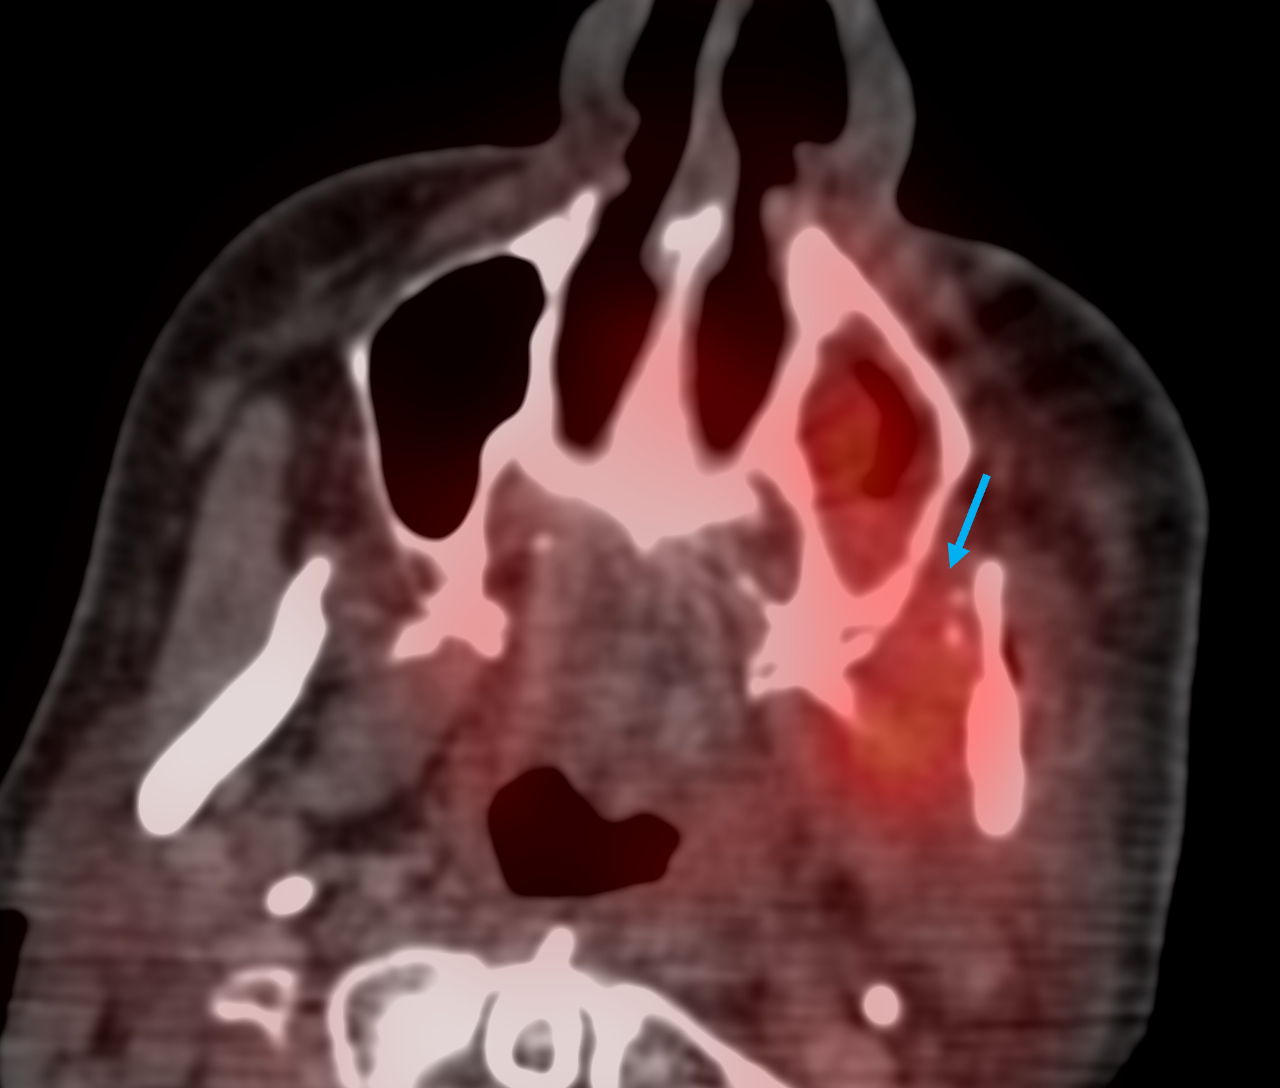

A 54-years old treated for left upper buccal squamous cell carcinoma had pain and difficulty in mouth opening.

PET/CT showed soft tissue but with minimal uptake in the left upper buccal space extending into the masticator space

It was decided to follow-up this lesion, since it was not clear, whether this was post-operative of tumor. 6 weeks later, a contrast CT shows minimal increase in the soft tissue